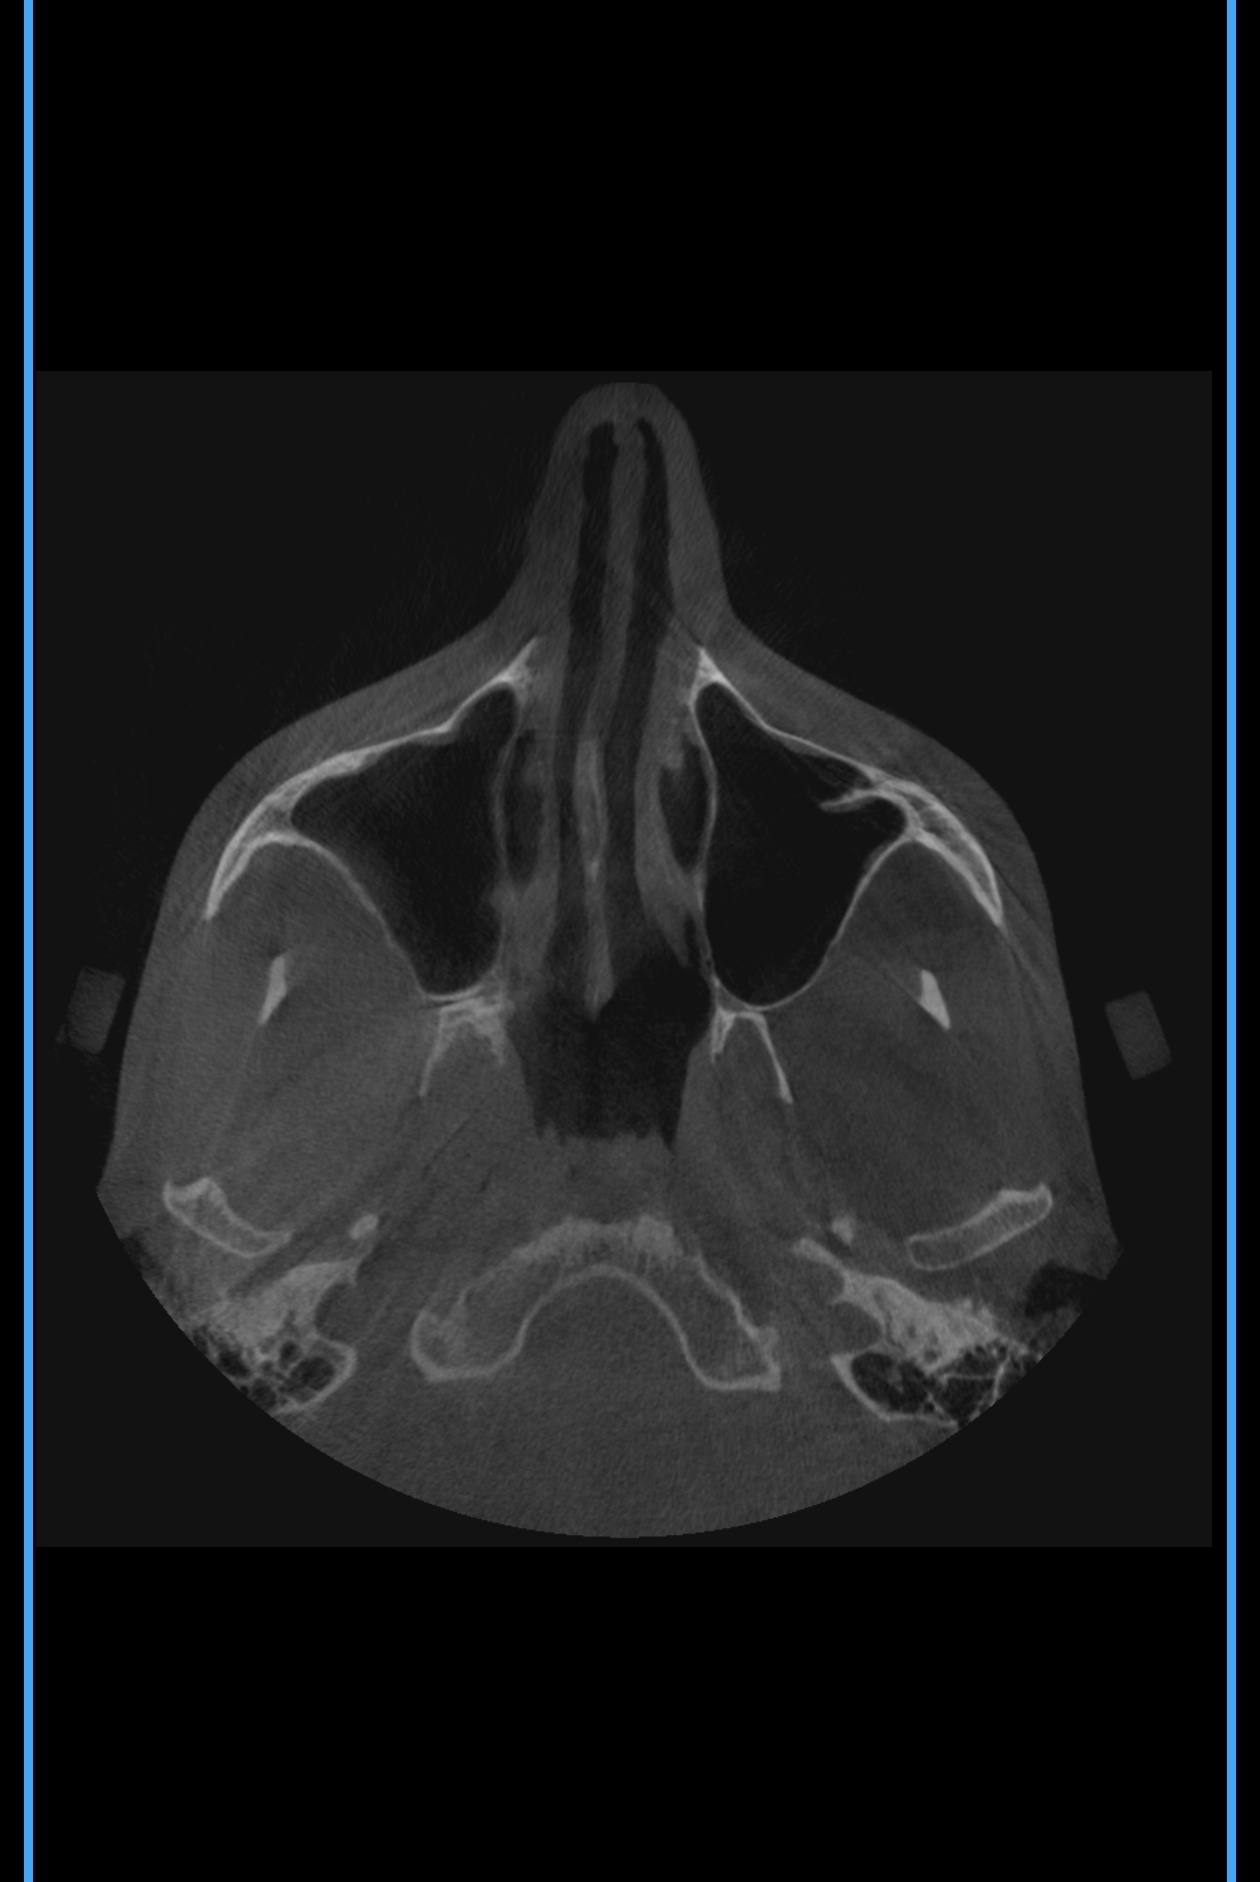

Тут же нужно выпрямлять носовые каналы или как это называется ? А то есть подозрение, что нудно будто бы всегда заложен и я чутка гундошу (когда слышу себя на записи)